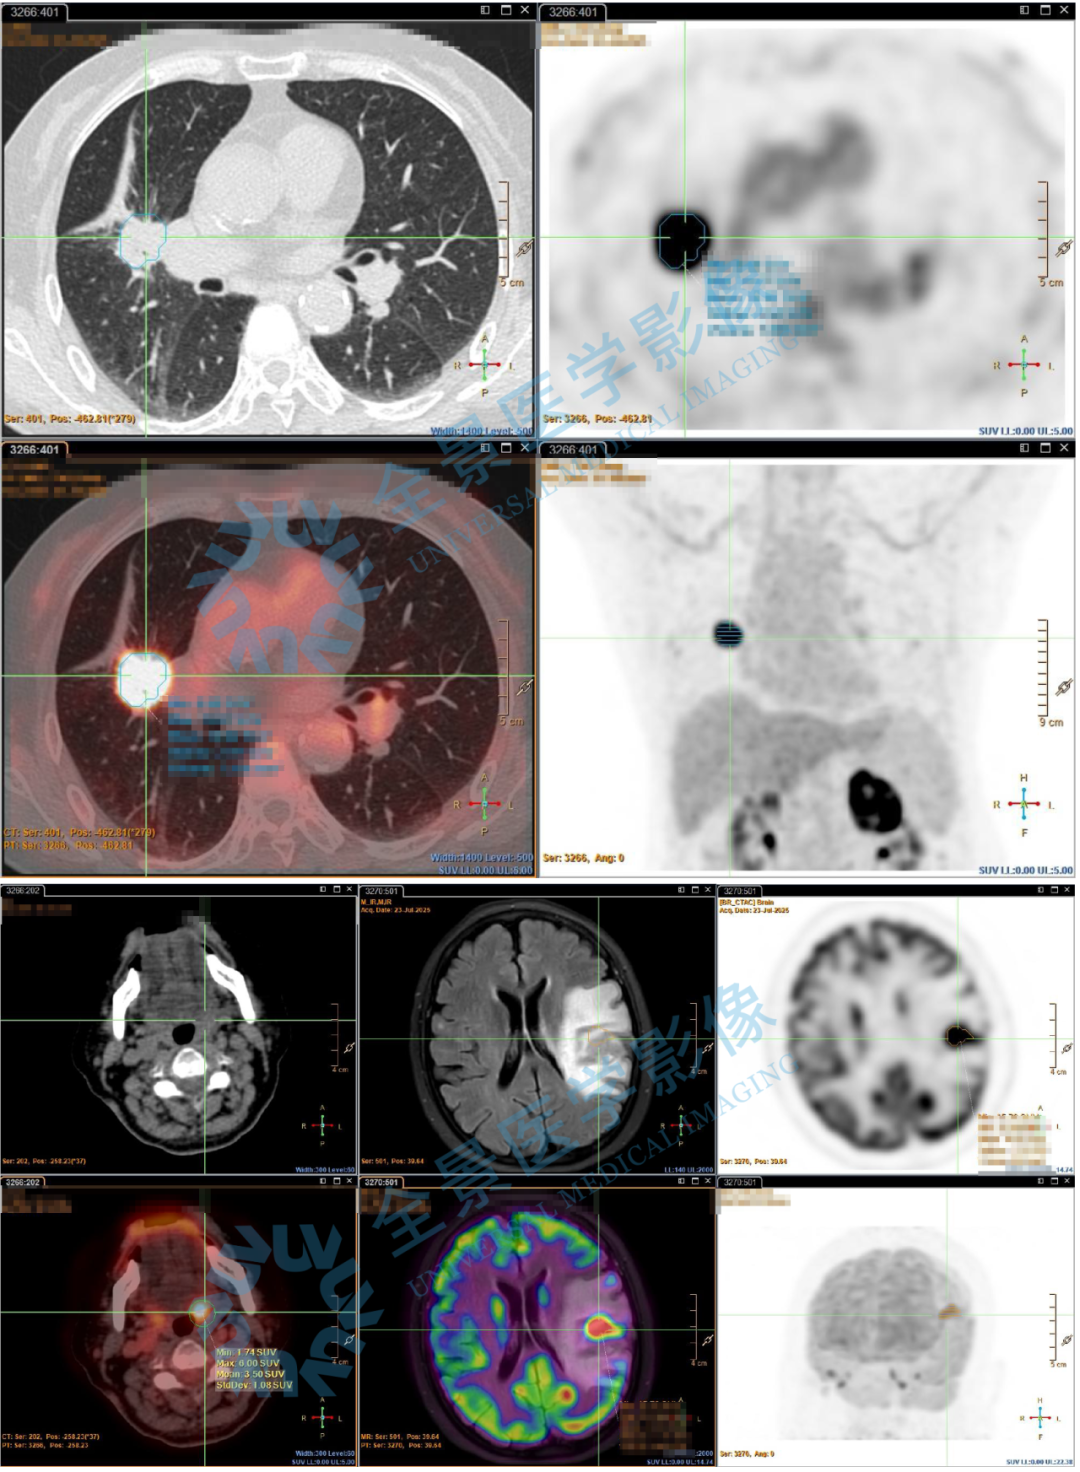

60 岁张女士(化名)近期感觉舌头麻木伴有吐字不清,行 MR 检查发现颅内占位,怀疑恶性。为了明确占位性质及全身情况,张女士来中心做 PET/CT 检查。

PET/CT 发现在张女士的右肺上段有一枚 FDG 摄取明显增高的肿块,影像考虑肺癌。颅脑占位 FDG 摄取明显增高并伴有其他信号,考虑转移瘤。不仅如此左肾也发现转移。

影像医生判断张女士为肺部肿块为原发灶,脑、肾脏为转移瘤,纵隔淋巴结怀疑转移,进一步监测复查。

因此,张女士在 PET/CT 扫描基础上,进行了 PET 多模态融合,将颅脑磁共振影像与 PET/CT 融合,获取更加精细化的病灶信息:

颅脑左侧发现转移瘤,右侧多发点、片状异常信号,考虑为变性灶(变性灶指因炎症、缺血、代谢异常等导致局部组织发生结构或功能改变的区域)。